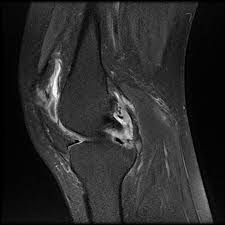

How To Read The Normal Knee Mri Kenhub

How To Read The Normal Knee Mri Kenhub from thumbor.kenhub.com

We scan axial (top to bottom) sagittal (right to left) and coronal (front to back). All of these may be good reasons to get a knee mri scan. Ultimately, the answer to this question is that it depends. In this video scott will take you through the procedure of receiving an mri for your knee. In other cases, it might take a few days. The test most often lasts 30 to 60 minutes, but may take longer. An mri scan can take between 15 to 90 minutes depending on which part of your body needs to be scanned. Why does mri take so long?